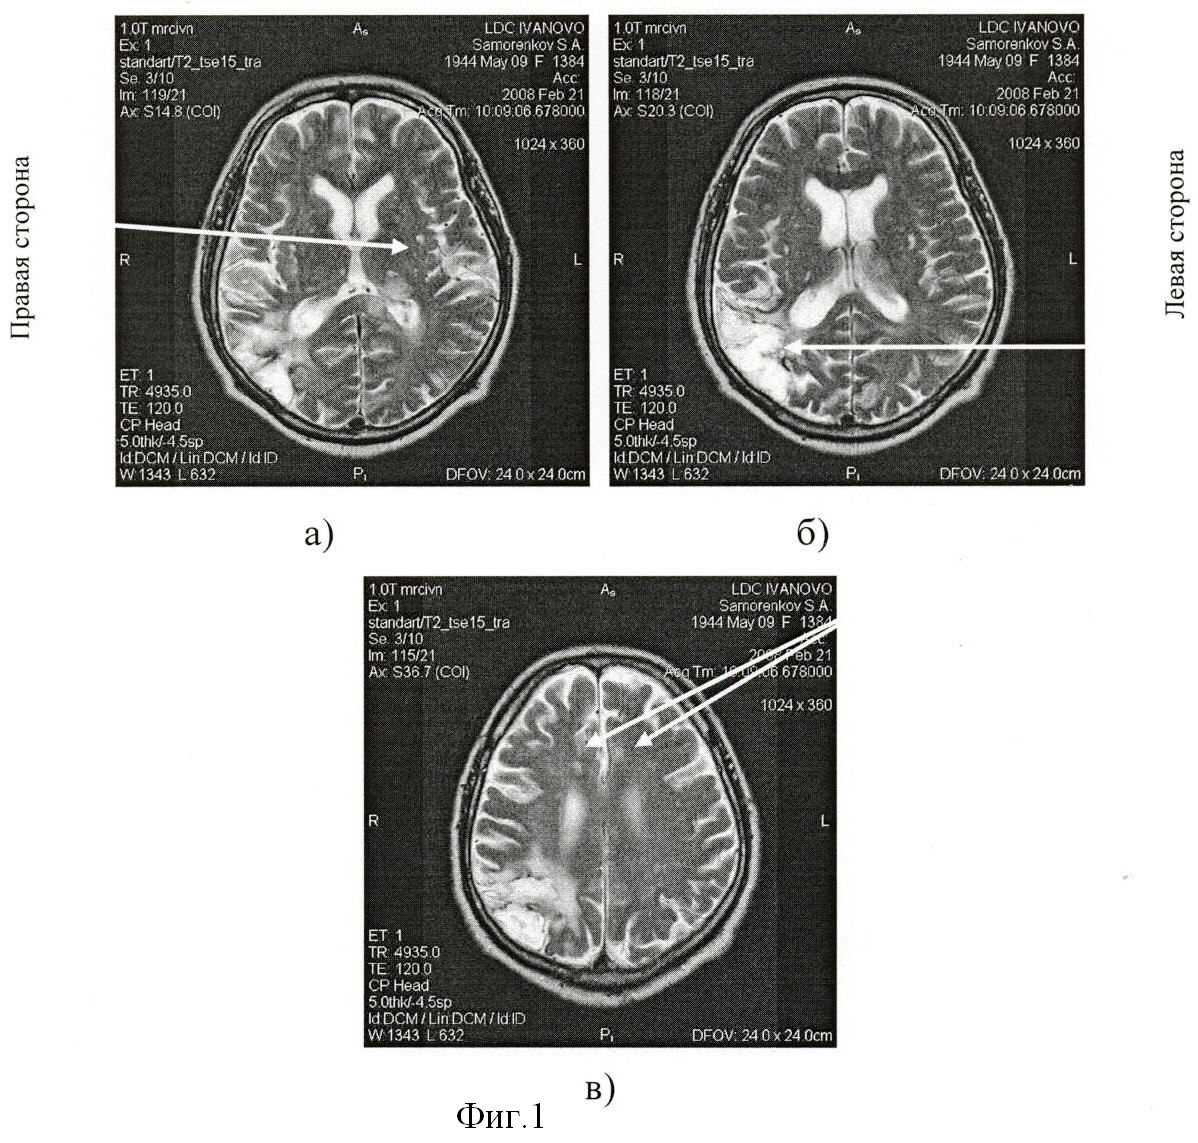

Визуально при магнитно-резонансной томографии выявили: округлая зона (фиг.1а) острого нарушения мозгового кровообращения по ишемическому типу в области таламуса слева размером 2,4×1,4×2,2 см; постишемическая клиновидная киста (фиг.1б) в субкортикальных отделах теменно-височно-затылочной области справа размером 7,3×4,6×6,1 см и множественные мелкие постишемические очаги (фиг.1в) в белом веществе субкортикальных и перивентрикулярных отделов лобных, теменных долей размерами до 0,8 см. Определили наличие смешанной заместительной гидроцефалии. Отметили многоочаговость и асимметричность поражения церебральных структур с локализацией очагов как в базальных отделах, так и субкортикальных зонах обоих полушарий мозга.